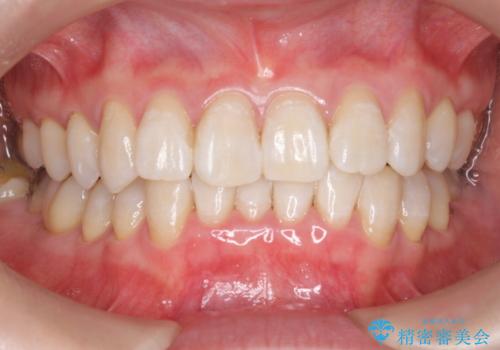

- クリーニング希望により来院されました。

PMTC30分コースを行いました。

人生で初めてのクリーニングということもあり、プラークや歯石が大量に付いていました。それにより、歯茎の腫れもあり出血も多かったです。これから矯正をスタートしていくため、歯ブラシ指導を行いホームケアを頑張ってもらっています。